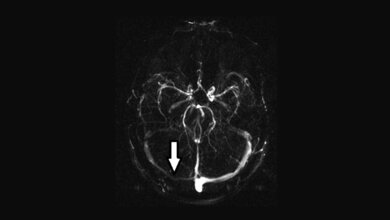

Bei Menschen mit einer besonderen genetischen Veranlagung führt dies dazu, dass sich Antikörper nicht mehr an eine ganz bestimmte Stelle des Protein VII, sondern fälschlicherweise an den sogenannten Plättchenfaktor 4 binden. Dadurch aktivieren die Antikörper Blutplättchen und lösen die Bildung von Blutgerinnseln aus. „Es ist so, als wenn bei einem Schlüssel ein Zacken verändert wird und der Schlüssel danach in ein anderes Schloss passt“ sagt die Co-Autorin Dr. Linda Schönborn von der Unimedizin Greifswald. „Diese Kombination aus zufälliger Mutation und genetischer Besonderheit kommt ausgesprochen selten vor. Daher ist auch das Risiko für diese Komplikation sehr gering.“ Nach derzeitigem Stand sei es allerdings nicht möglich, Menschen im Vorfeld zu erkennen, die nach einer Impfung VITT entwickeln.